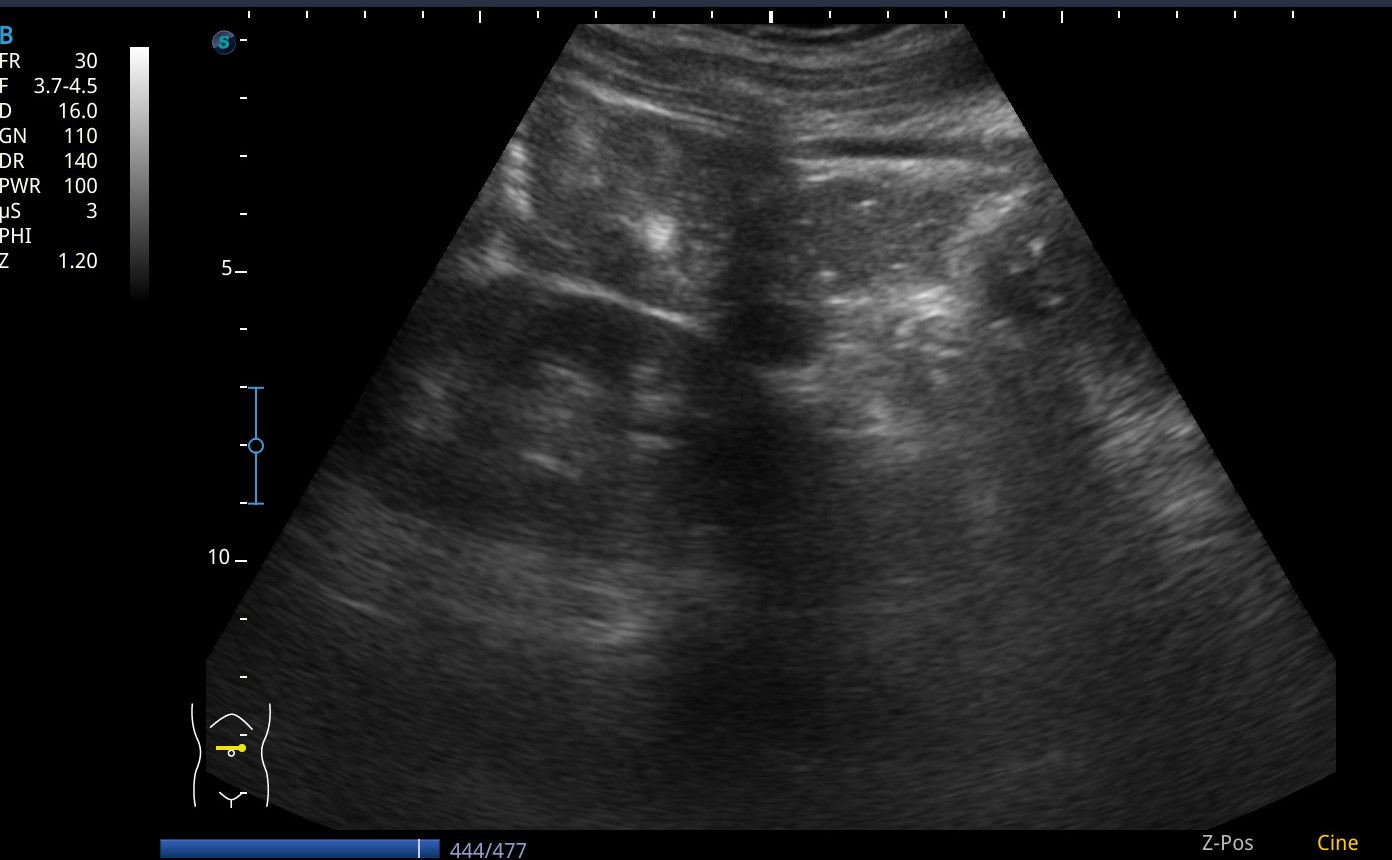

Se realiza ecografia a pie de cama que muestra como en el flanco derecho presenta silueta renal con un polo superior visible, sin poder definir el polo inferior, y la misma imagen en la silueta renal izquierda.

Asi mismo vemos a nivel de epigastrio bajo (zona umbilical), tejido sugestivo de parénquima renal que cruza por delante de grandes vasos, imagen compatible con un riñon en herradura.

En pelvis renal izquierda se aprecia una imagen hiperecogénica, sugestiva de microlitiasis.